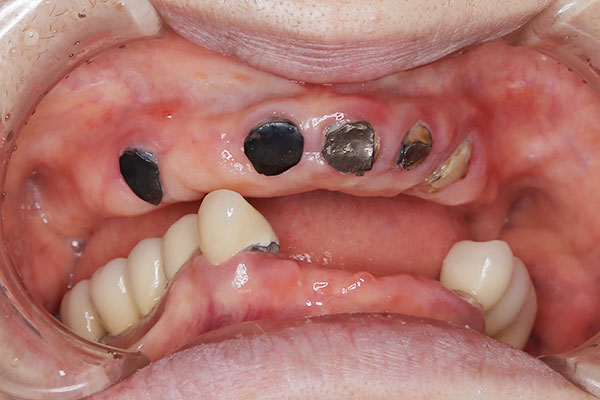

• 治療前

• 治療後

上顎6本、下顎6本。¥6,589,000

多くの歯に重度の虫歯や歯周病がみられたケース。歯周病の治療を行いAIl-on-6による包括治療を行った。